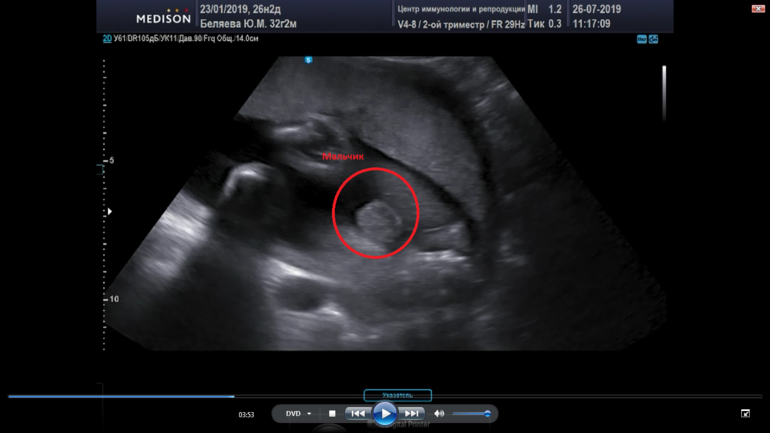

У меня, если что, вот так выглядели. Это дочка.

Это сынок. Тут в кадре только мошонка. Писюн сверху (в кадр не попал).Обе фотки - стоп-кадры видео, как бы вид снизу между ножек.